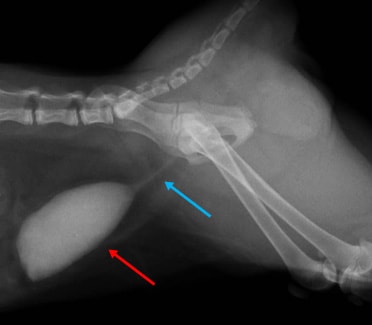

尿道形成術

尿道形成術 ( 症例-1 )

何らかの原因で、正常な尿道の構造が維持できない状態の時に尿道形成術を行います。

猫ちゃんでは尿石症により、結石が尿道につまるのを何度も繰り返してしまう場合、この手術が適応されます。

下記の症例は、先天的に尿道が変形しており、日に日に尿道がふさがってしまい、尿道閉塞を起こしてしまった猫ちゃんです。メスの膣とオスの精巣の両方の生殖器を持っていた奇形です。

尿道形成術を行い、現在は元気に過ごしております。

![]() |

逆行性尿道造影を行ったレントゲン写真です。膀胱(赤矢印)、腹腔内の尿道(黄矢印)は正常に造影されています。 |

|